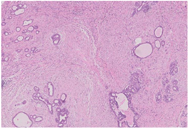

大体检查:切除乳腺肿瘤及周围少许乳腺组织,大小共2 cm ×1.5 cm ×1.5 cm,肿瘤直径约1.5 cm,切面灰白色,质地较硬,与周围组织分界不清。镜下检查:肿瘤缺乏包膜,境界不清、浸润周围乳腺组织。肿瘤内有密集增生的梭形细胞,但缺乏过度增生。梭形细胞有中度异型性,核分裂约1~2个/10 HPF,可见病理性核分裂像。肿瘤内有导管增生,少部分扩张、呈裂隙状,无分叶状结构。肿瘤内靠近边缘可见扩张的小管,呈浸润性分布,周围肌上皮缺失,细胞形态温和、有顶浆分泌,无核分裂。免疫组织化学检查:梭形细胞CD10与SMA有不同程度的阳性表达,Ki-67阳性指数约30%~40%,其余所染标志物均阴性。小管周围CD10、Calponin、P63、CK5/6均阴性,显示肌上皮缺失,Ki-67阳性指数约3%,ER与PR弥漫强阳性,Her-2(0)。

诊断:(左侧)乳腺交界性叶状肿瘤,其内有浸润性小管癌。鉴别诊断:(1)乳腺叶状肿瘤并发浸润性小管癌确实极易漏诊,主要原因是浸润性小管癌形态温和,恶性特征不明显,因此,需与并发于叶状肿瘤内的放射状硬化性病变、盲管性腺病等鉴别。与这些良性病变鉴别的主要特点是肿瘤性小管呈浸润性分布。此时,判断肌上皮缺失与否在鉴别中具有十分重要的价值,需要辅以免疫组化P63、Calponin等染色明确。(2)另外小管癌也需与非特殊型1级浸润性乳腺癌鉴别,因为前者预后更好。小管癌腺体呈卵圆形、尖角状末端以及顶泌胞质突起,一般情况下,非特殊型1级浸润性乳腺癌不具备这些特征。